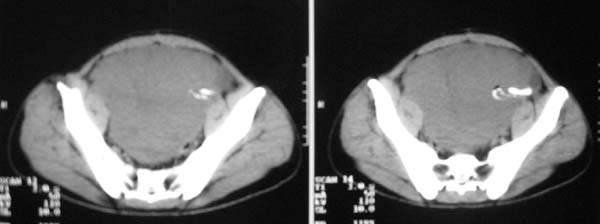

以下是引用zjzjr在2007-9-27 22:20:00的发言:[br]肠腔受推移,未见明显扩张及液平,所以考虑是肠外病灶, 间叶源性肿瘤?脂肪瘤?建议增强。

以下是引用guzhongliangddd在2007-9-27 23:21:00的发言:[br][br]与肠内高密度相同,病灶应该没有钙化,我认为首先考虑是间叶组织的良性肿瘤。建议楼主做后重建观察。中线区域大血管旁未见确切增大淋巴结。病灶对肠道只是推移关系。

以下是引用余辉在2007-9-27 22:24:00的发言:[br]暂考虑肠道间质来源肿瘤如小肠平滑肌肉瘤/瘤可能,应该增强